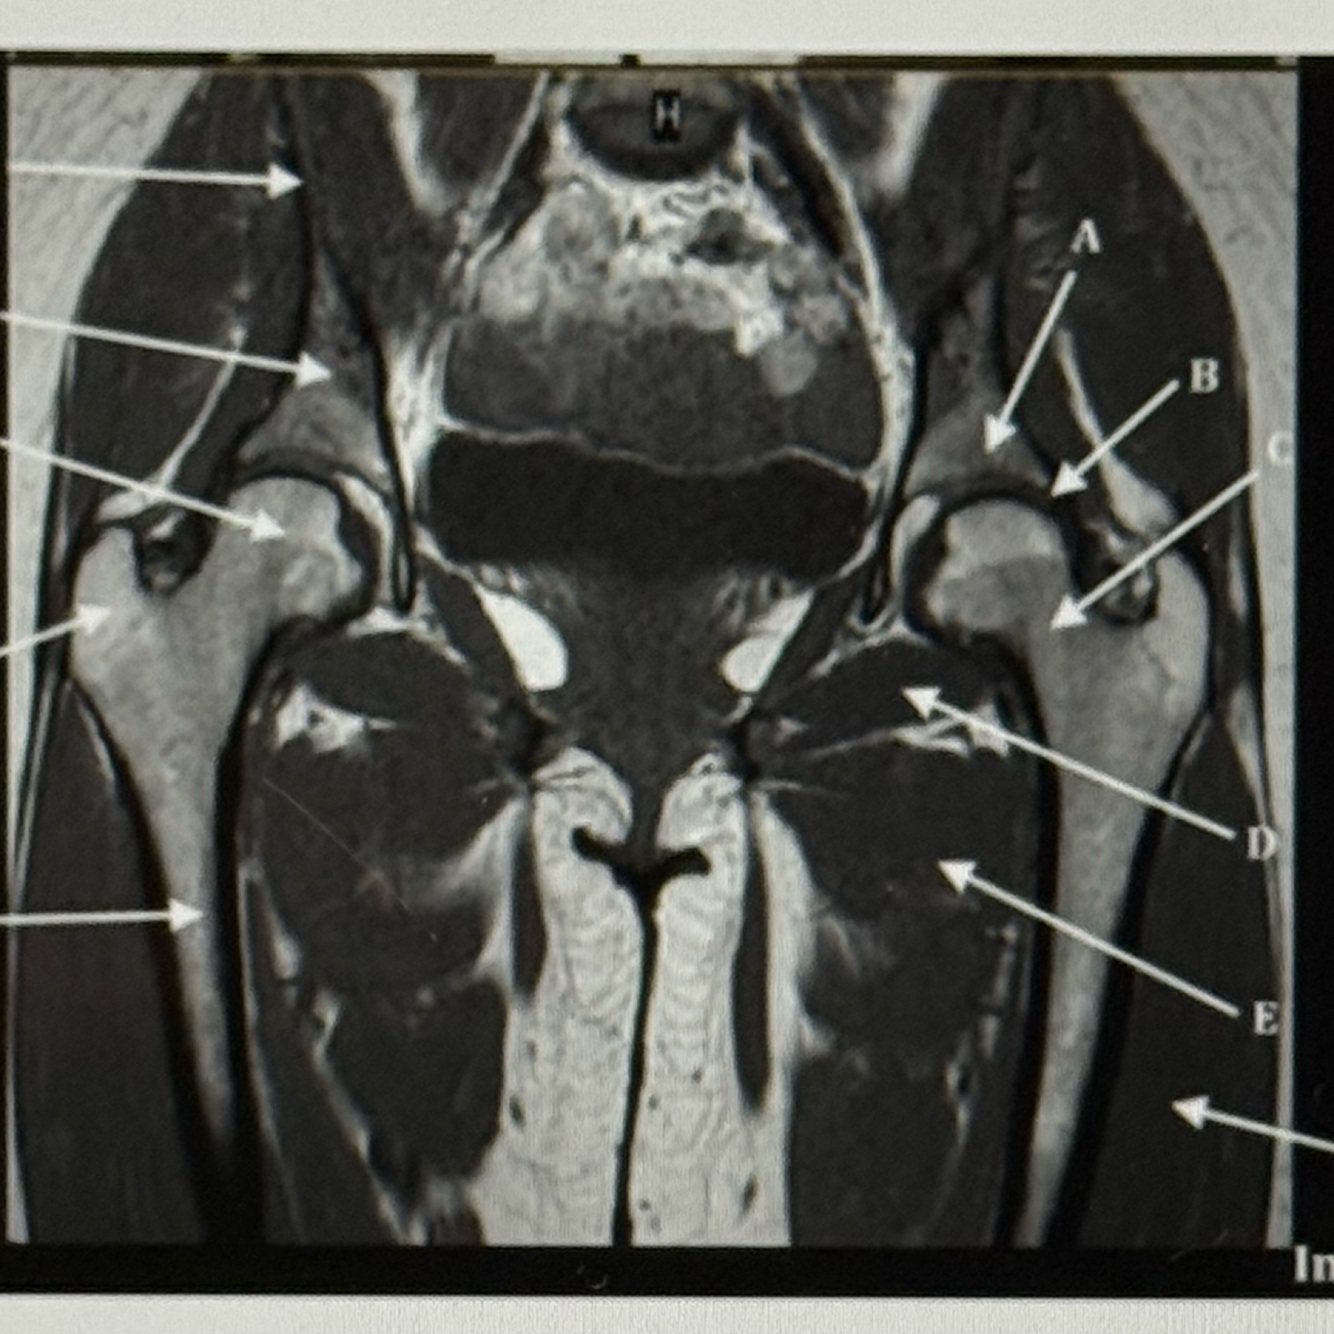

Letter D points to

Acetabulum

Letter E points to the

Ischium

Letter G points to the

Superior pubic ramus